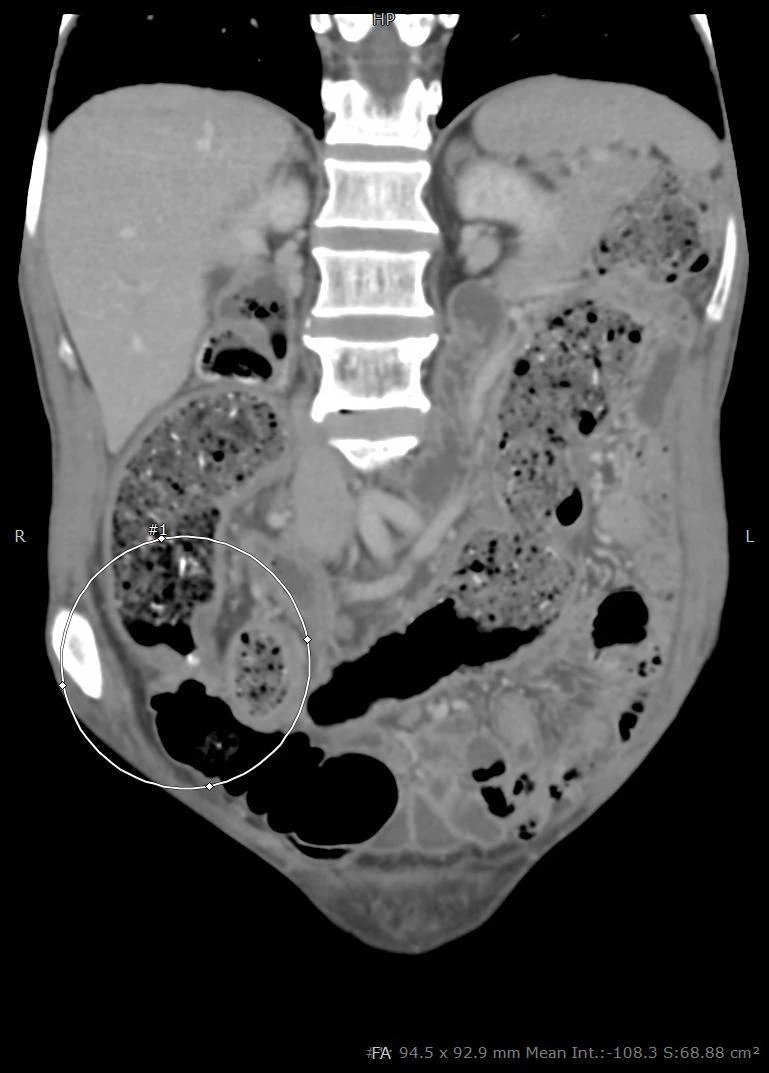

Hình chụp CT cho thấy người bệnh có khối u đại tràng trái. Ảnh: BVCC

Tại BV, bác sĩ  khám, xét nghiệm và chụp CT bụng phát hiện khối u đại tràng trái rất to, di căn hạch và biến chứng gây tắc ruột, các quai ruột giãn rất to nguy cơ vỡ đe dọa tính mạng bệnh nhân.